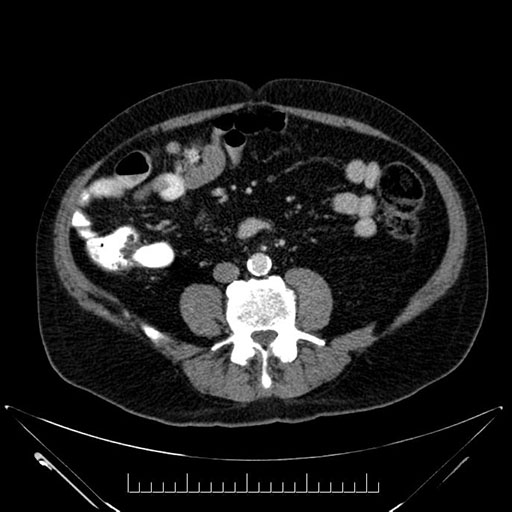

Whipple (pancreaticoduodenectomy) [case 7]

Imaging Analysis

Look through the patient's CT scan to identify any areas of concern for the necessary procedure.

Axial - stented